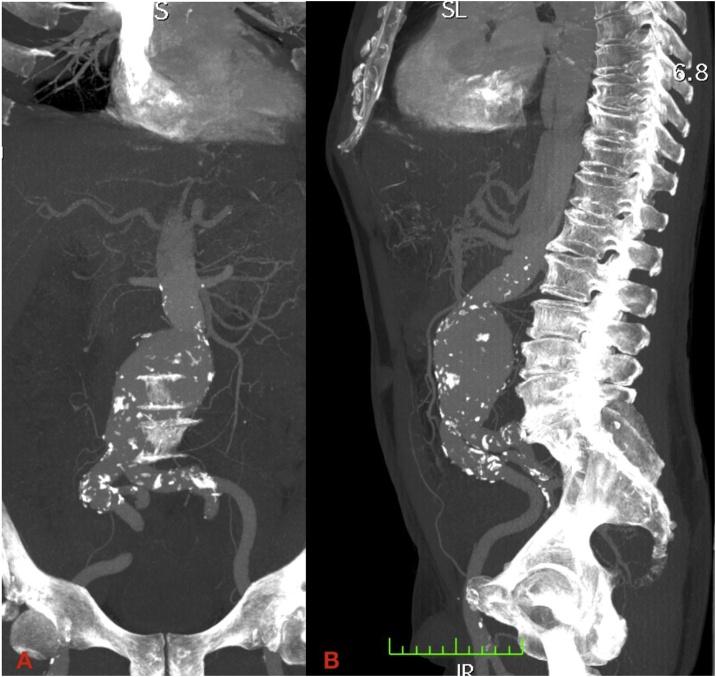

同步症状性急性B型主动脉夹层和大型肾下腹主动脉瘤的同期血管内治疗。技术要点及病例报告。

Simultaneous endovascular treatment of synchronous symptomatic acute type B aortic dissection and large infrarenal aortic aneurysm. Technical tips and case report.

CASE PRESENTATION

We report a complicated case of a symptomatic patient presenting with a type B aortic dissection and false lumen extension into superior mesenteric artery (SMA) with an infrarenal abdominal aortic aneurysm (AAA). Severe back pain and hypertension were the patient's initial complaints. This patient underwent endovascular repair with a thoracic and infrarenal aortic endograft.

我们报告一例复杂病例,一名有症状的患者表现为B型主动脉夹层,假腔延伸至肠系膜上动脉(SMA),同时伴有肾下腹主动脉瘤(AAA)。患者最初的症状是严重背痛和高血压。该患者接受了胸主动脉和肾下腹主动脉腔内修复术。